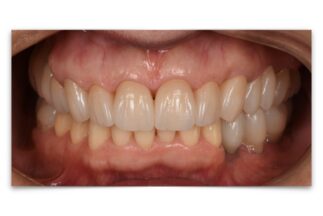

- After

【症例ステータス】

| 年齢 | 性別 | 治療期間 | 治療費概算 |

|---|---|---|---|

| 57歳 | 女性 | 2年 |

480万 ※費用は範囲によって異なります。 |

| 主訴 | |

|---|---|

| 治療内容 | 上顎右側サイナスリフト インプラント埋入上顎3本 下顎3本 上部構造モノリシックジルコニアクラウン修復 |

| リスクについて | インプラント周囲炎 スクリューの緩みなど |